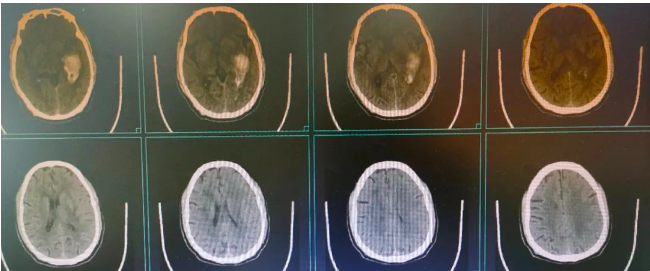

近日医院神经外科一患者,男性,59岁,因“突发头痛、头晕5天,加重伴恶心、呕吐3天”入院,入院查体: BP:162/93mmHg 一般情况及精神差,神志清楚,言语利索,双瞳等大同圆,直径约3.0mm,光反射存在, 四肢肌力正常,生理反射存在,病理反射未引出。门诊头颅CT提示左侧颞叶脑出血,并周围水肿形成。

患者既往有高血压病史,发病后无偏瘫、失语、口角歪斜等功能区脑出血症状,一直以感冒在家口服“头痛粉、感冒药”治疗,一开始症状有所缓解,未再进一步就诊,后脑水肿加重,头痛、呕吐明显,口服药物无效才进一步就诊。